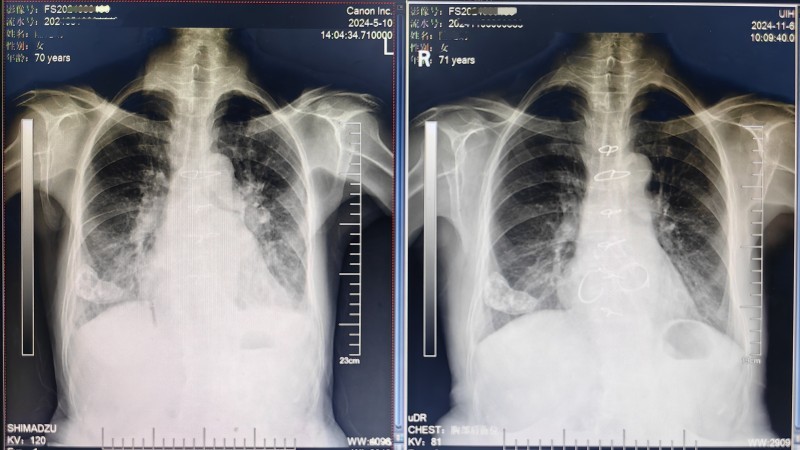

(图片9:术后胸片对比,正侧位对比)

在后续的连续随访过程中,患者的两个瓣膜功能状态良好,达到了术前预期,术后平均跨瓣压差越来越接近完美。

此次手术过程顺利,切除原生物二尖瓣、主动脉瓣耗费时间较多,但植入新的生物瓣膜时使用免缝合瓣膜完成,大大缩短了手术时间。术后当晚患者已拔除气管插管,第1天即可下地活动,超声复查显示置换的免缝合主动脉瓣生物瓣膜功能正常,术后3周出院。